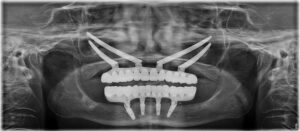

Atunci când nici adițiile osoase nu mai funcționează, apelăm la implanturi speciale, numite implanturi zigomatice.

Implanturile dentare zigomatice sunt implanturi lungi ce se inserează la maxilar, (osul pometelui). Acestea se folosesc în cazul în care resorbția osoasă în zona maxilarului este severă. pentru mai multe detalii despre implanturile zigomatice puteți viziona acest videoclip.

În timpul intervenției chirurgicale au fost inserate 4 implanturi zigomatice în maxilar, și 4 implanturi convenționale la mandibulă. Acestea au fost suficiente pentru a susține o dantură completă și funcțională!